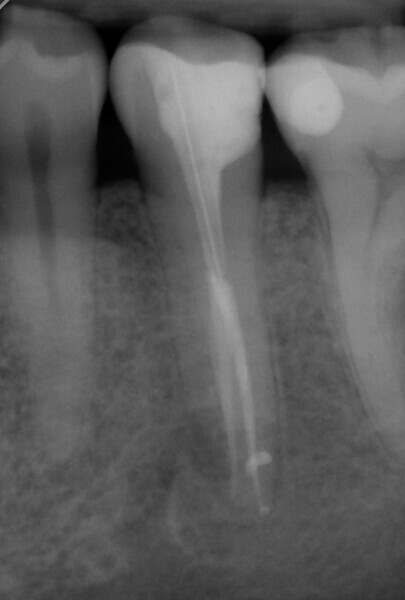

Obturation and final restoration with a fibre post were performed at the second appointment. The radiograph confirmed that I had been able to treat both root canals along the entire length of the tooth (approximately 23 mm) with minimal loss of tooth structure and in the most conservative manner possible (Fig. 6).

The follow-up appointments observed complete healing of the treated tooth (Fig. 7). Together with the patient, we decided that a crown was not necessary for the moment.